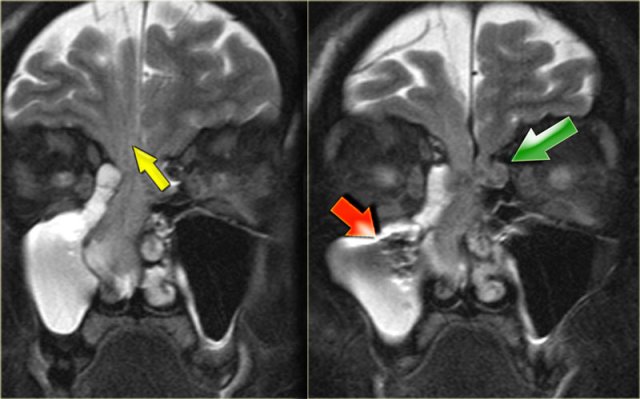

Encephalocele Encephalocele

Encephalocele

Coronal T2WI of the patient on the left show an abnormal structure in the right nasal cavity.

When you've decided what it is, then stop to think about whether the abnormality is developmental or acquired.

This patient has an encephalocele.

There are two findings on the images that let you know that this is developmental.

First of all, notice the smaller encephalocele on the left side (green arrow).

Acquired encephaloceles are more often than not unilateral.

The second clue is the cortical dysplasia (yellow arrow) as part of a migrational abnormality.

Acquired encephaloceles (ie after surgery) tend to lead to dead gliotic brain, which would have a high signal intensity on T2WI.

The strange looking structure in the left image (red arrow) is surgical packing, placed there after the involuntary encounter with brain tissue.

Encephalocele Sag T1WI. Encephalocele Sag T1WI.

The blue arrow points to the sphenoid sinus which is hyperintense, due to mucoid impaction as a result of obstruction by the encephalocele.